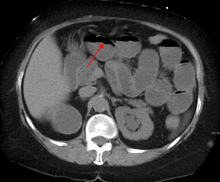

Causes of bowel obstruction include adhesions, hernias, volvulus, endometriosis, inflammatory bowel disease, appendicitis, tumors, diverticulitis, ischemic bowel, tuberculosis, and intussusception.[3][1] Small bowel obstructions are most often due to adhesions and hernias while large bowel obstructions are most often due to tumors and volvulus.[3][1] The diagnosis may be made on plain X-rays; however, CT scan is more accurate.[3] Ultrasound or MRI may help in the diagnosis of children or pregnant women.[3]

The main diagnostic tools are blood tests, X-rays of the abdomen, CT scanning, and/or ultrasound. If a mass is identified, biopsy may determine the nature of the mass.

Contrast enema or small bowel series or CT scan can be used to define the level of obstruction, whether the obstruction is partial or complete, and to help define the cause of the obstruction.